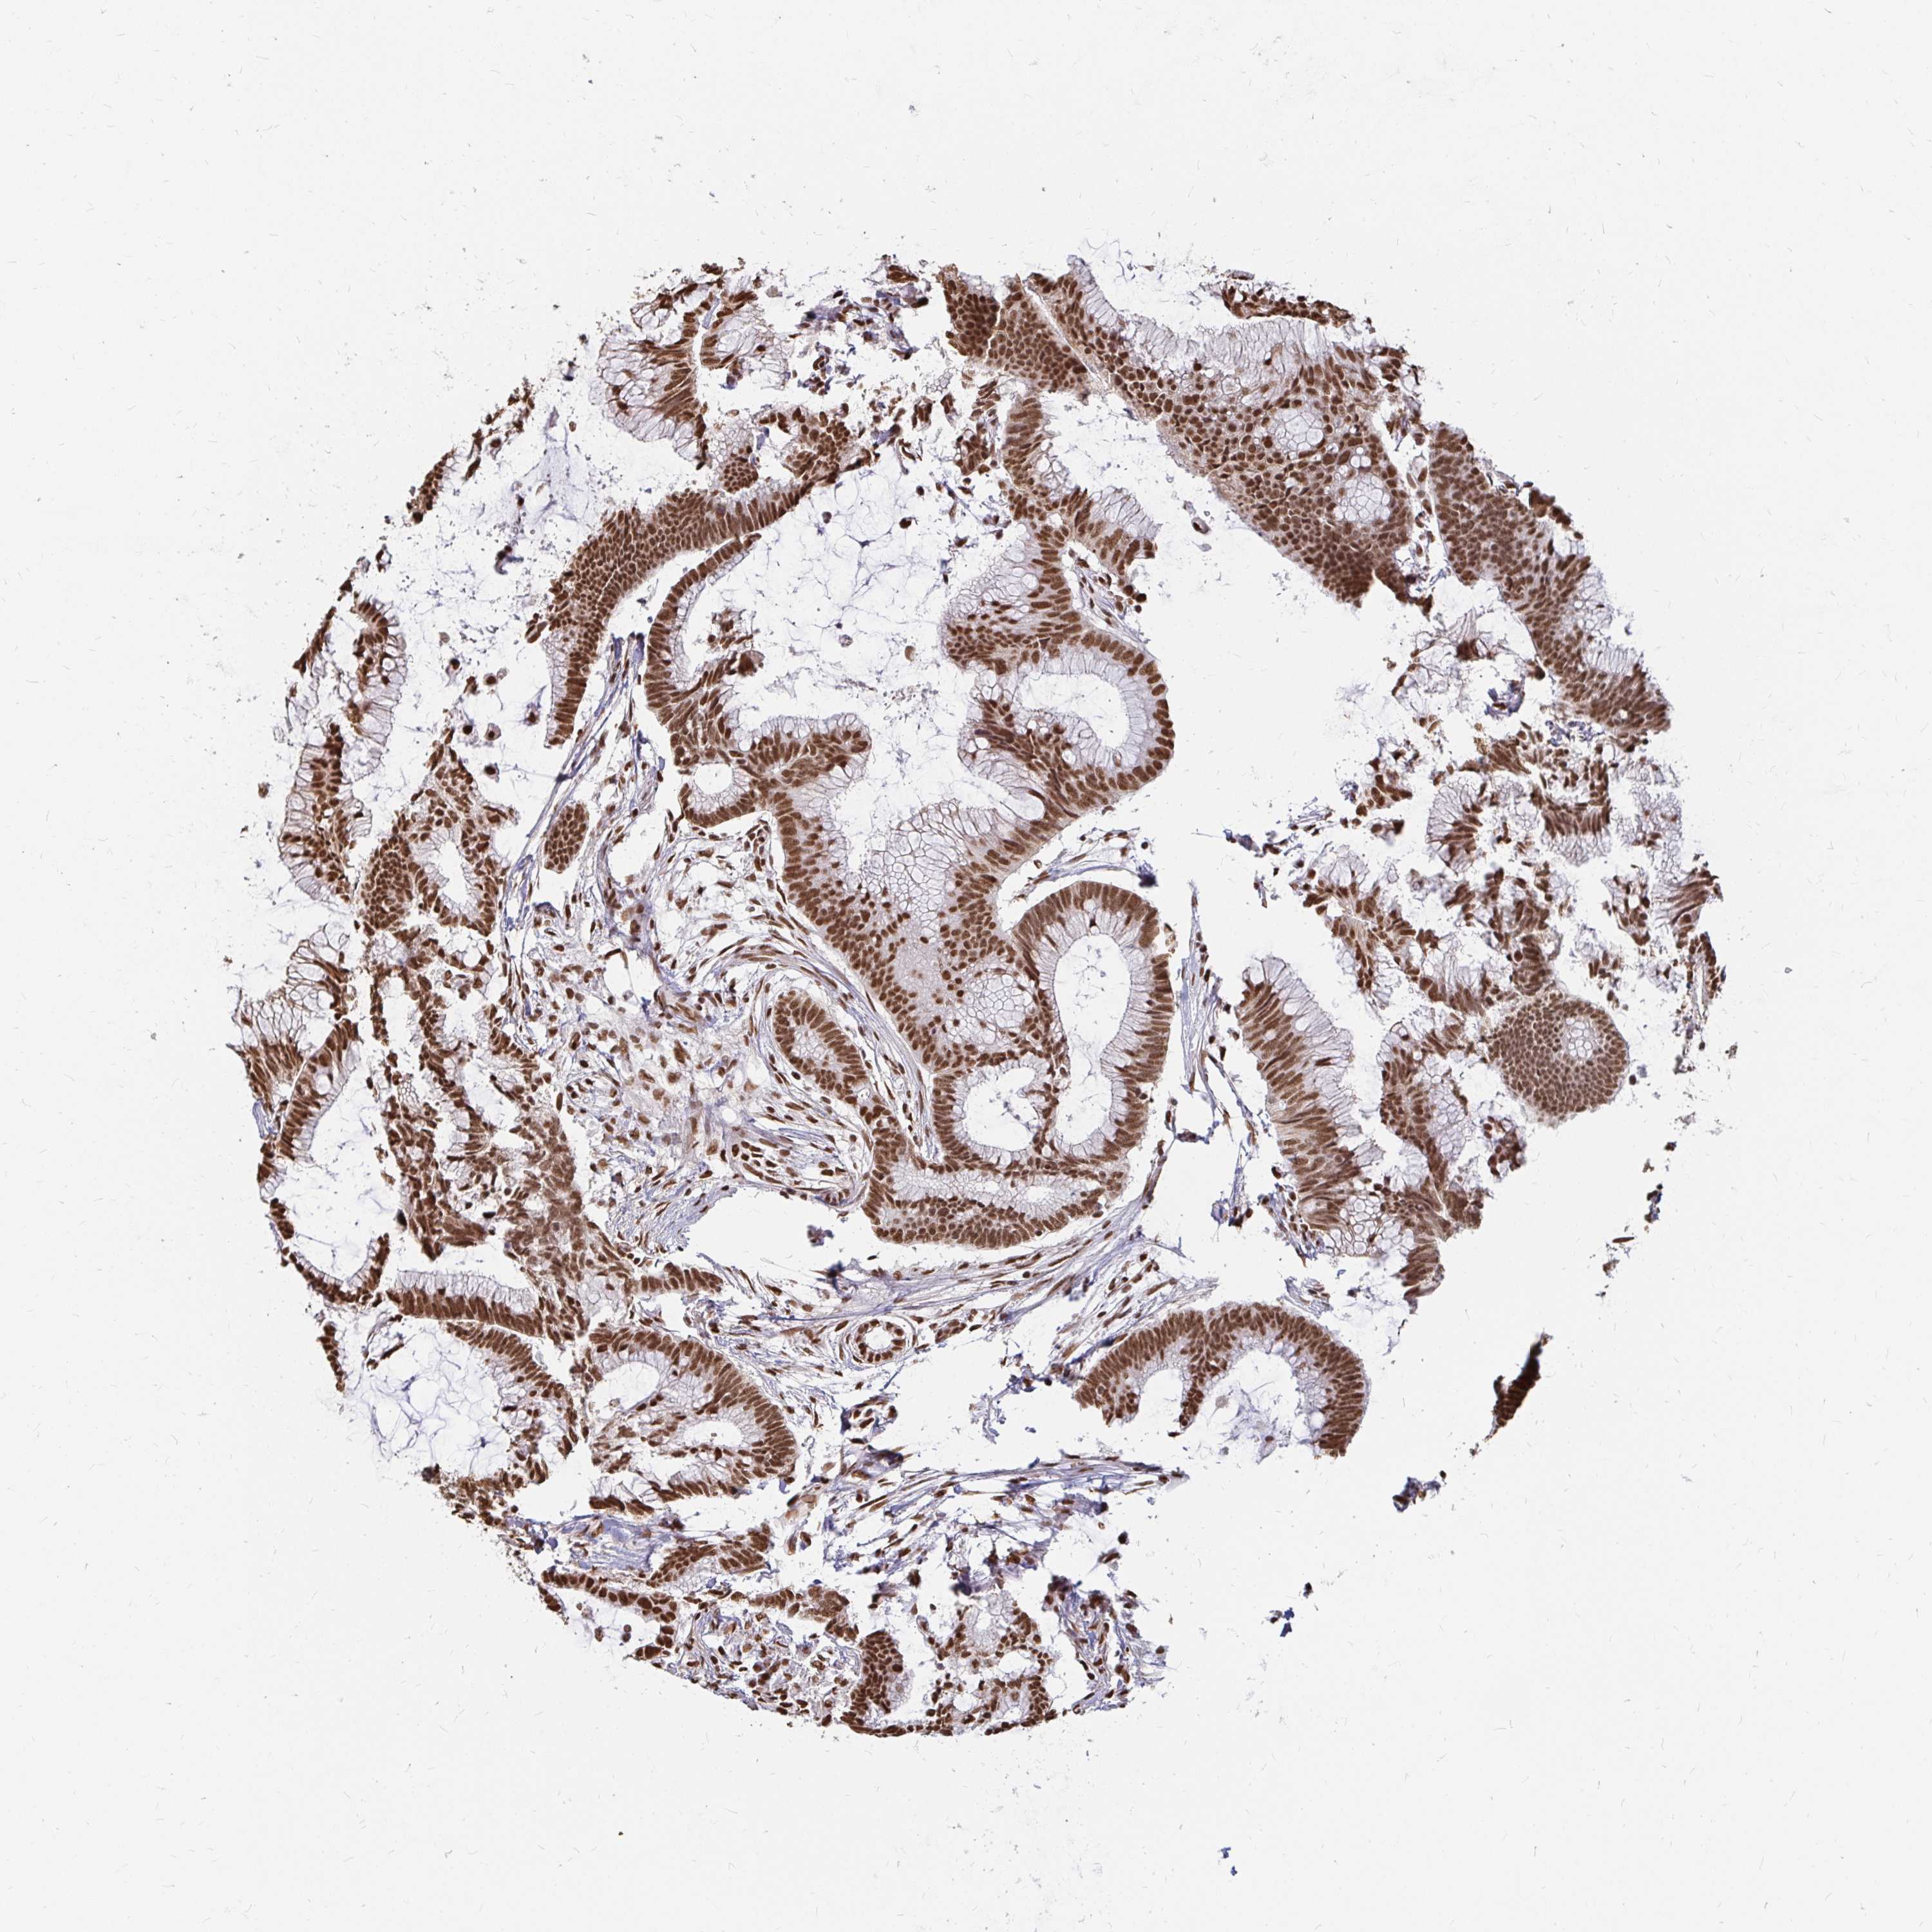

CANCER COLORECTAL CANCER Show tissue menu

Colorectal cancer

Human cancer

Colon adenocarcinoma